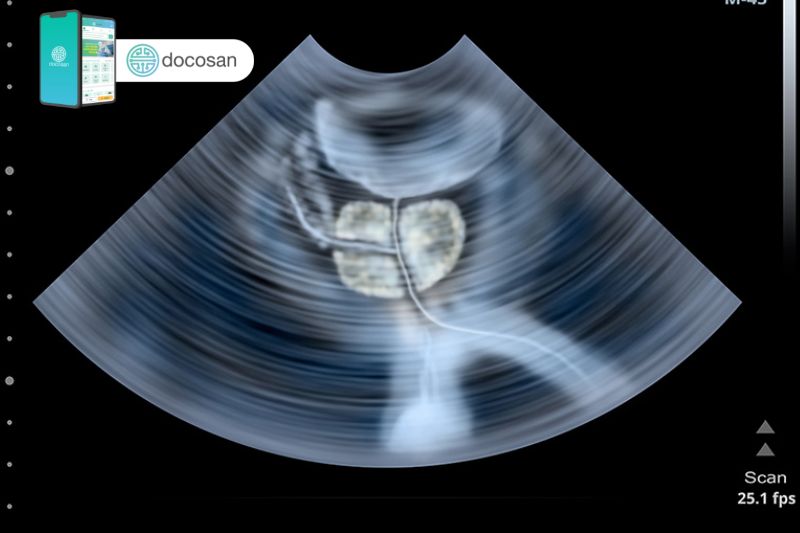

Thăm trực tràng là một các thăm khám lâm sàng bằng cách bác sĩ sẽ đưa một ngón tay vào trực tràng để kiểm tra xem kích thước tuyến tiền liệt có to lên không và có xuất hiện khối bất thường nào không. Trước khi sinh thiết tuyến tiền liệt thì bác sĩ nam khoa cũng có thể chỉ định siêu âm tuyến tiền liệt của nam giới qua đường trực tràng.

Hiện đại hơn là khi các kỹ thuật sinh thiết tuyến tiền liệt có thể được thực hiện dưới sự hướng dẫn của chẩn đoán hình ảnh như: siêu âm, chụp cắt lớp vi tính, chụp cộng hưởng từ.